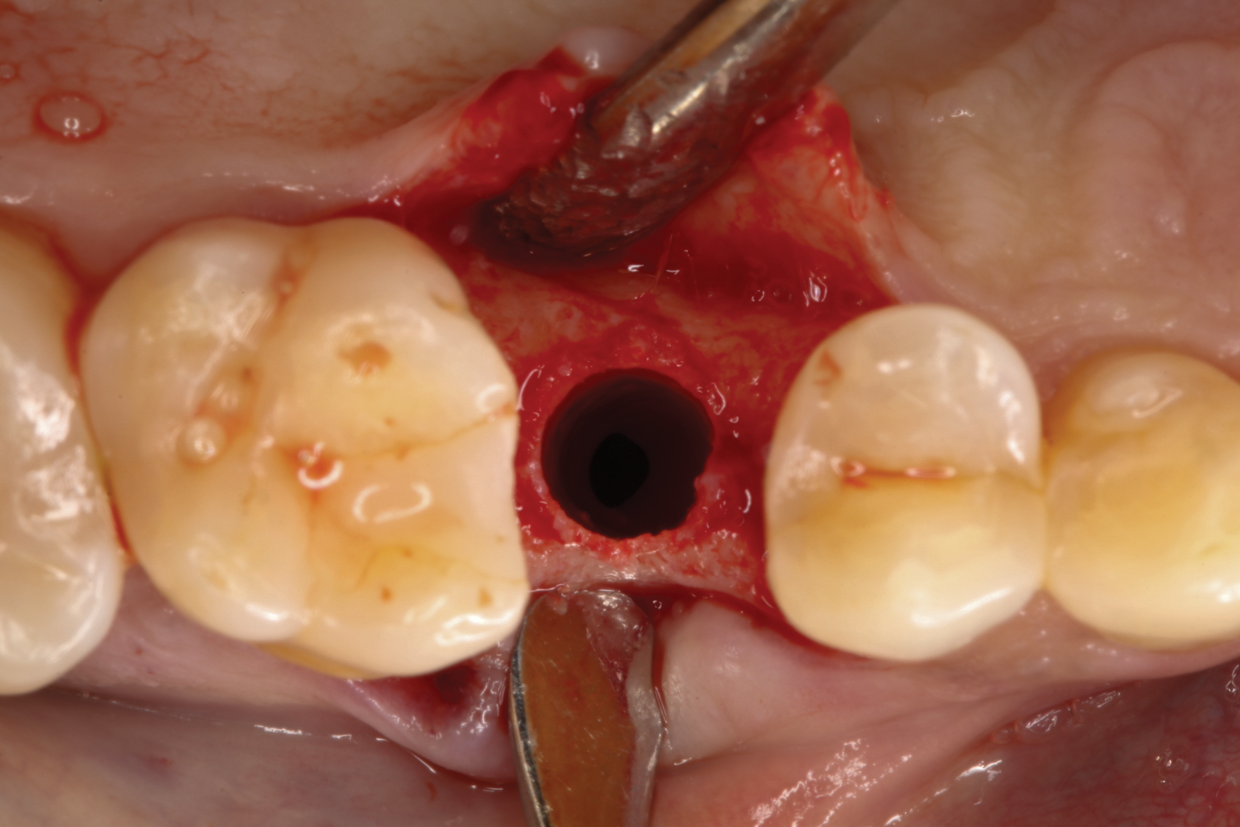

Fig 2. Minimally traumatic exodontia was performed to preserve the integrity of the socket walls and adjacent soft tissue.

Figure 2

Following local anesthesia via infiltration of 2% xylocaine with 1:100,000 epinephrine, a sulcular incision was carried out on both the buccal and lingual aspects of the tooth to protect adjacent soft tissues during tooth elevation. Periotomes were used following the long axis of the tooth to provide careful elevation of the residual root of the maxillary second premolar. After tooth removal, the extraction socket was inspected and completely degranulated with curettes. A saline solution was used to irrigate the site, and bleeding from the socket walls was stimulated (Figure 2).